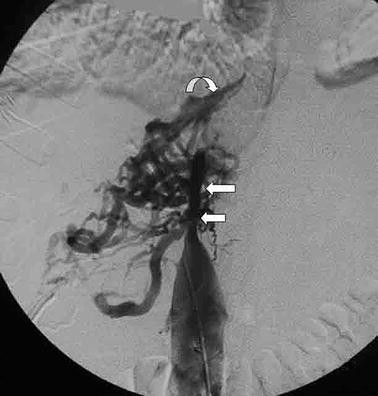

portal vein embolization

what is REILD

radioembolization-induced liver disease, may happen after transarterial radioembo (TARE), aka Y-90

4-8 wk after treatment

jaundice and ascites (life threatening).

supportive care

REILD = Hepatomegaly with heterogeneous parenchymal enhancement and randomly distributed ill-defined hypoattenuating or hypointense areas in portal venous phase, usually associated with development of ascites